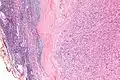

| Micrograph of an intranodal palisaded myofibroblastoma. H&E stain. | |

IPMs are diagnosed by examination of the tissue by a pathologist. They have a rim of peripheral lymphoid tissue (remnant of a lymph node) and consist of spindle cells with nuclear palisading. Red blood cell extravasation is common and blood vessels surrounded by collagen with (fine) peripheral spokes (amianthoid fibers) are usually seen.[2]

Immunostains for smooth muscle actin and cyclin D1 are characteristically positive. The main histologic differential diagnosis is schwannoma.